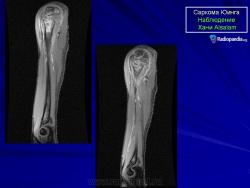

Периостальная саркома Юинга бедра.